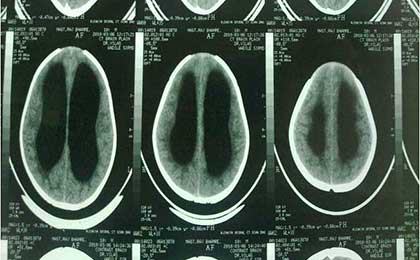

Arrested Hydrocephalus CT

Arrested Hydrocephalus

Arrested Hydro T2W

Arrested Hydro 3 Lat

Arrested Hydro 2